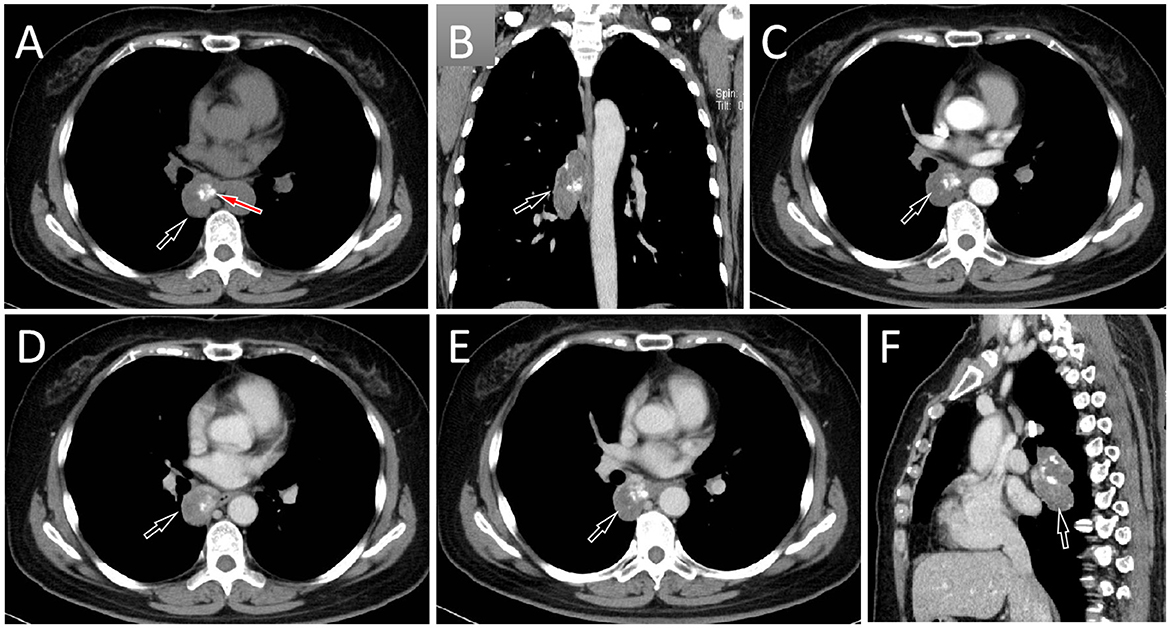

A 57-year-old female patient accidentally discovered a soft tissue mass in her posterior mediastinum during a physical examination in an outside hospital on 11 November 2023. She consciously had no obvious clinical symptoms and was not paid attention to, nor was undergoing any treatment. On 20 April 2024, the patient came to our hospital for medical help due to a cough and chest tightness. The physical examination did not reveal any positive signs. She and her family have denied any history of cancer or major genetic disorders. The serological laboratory test results revealed that the treponema pallidum antibody was positive, while other results, including blood routine, liver and kidney function, and serum tumor markers, were all negative. She had a history of syphilis 15 years ago; the condition resolved completely following treatment, and there are currently no clinical or serological indications of recurrence. She denied any history of tuberculosis, hepatitis, or malignancies. The patient underwent chest computed tomography (CT) examination (Figure 1) on April 24, which revealed a well-defined soft-tissue density mass in the posterior mediastinum with calcification. Contrast-enhanced CT showed a slight enhancement of the mass, suggesting a possible neurogenic tumor. The patient underwent surgical complete resection of the tumor through thoracoscopy under general anesthesia on April 26 after completing the preoperative routine examination. During the operation, the tumor was found to be located between the spine, azygos vein, trachea, and esophagus, with a size of approximately 6 cm × 4.5 cm × 4.0 cm, spindle-shaped, with a complete capsule and no obvious adhesion to surrounding structures. The tumor was gradually separated along its edges using an ultrasonic knife until it was completely removed, and then sent for pathological examination. Hematoxylin–eosin staining (as shown in Figure 2) showed that the excised tumor tissue appeared as a gray–red envelope block with intact capsule, medium texture, and calcified lesions in some areas. No tumor invasion was observed at the resection margin. Immunohistochemistry revealed tumor cells positively expressed vimentin, Cluster of Differentiation 34 (CD34), cytokeratin (CK), and CD56, while they negatively expressed insulinoma-associated protein 1 (INSM1), S100, CD68, and so on. Based on these histopathological findings of the patient, she was diagnosed with PES. After surgery, the patient did not receive further radiotherapy, chemotherapy, or other treatment methods. At 4 months after discharge, a chest CT examination revealed a new soft tissue density nodule at the site of her previous surgery. In order to further evaluate the nature of the nodule and determine the next treatment plan, the patient underwent 18F-FDG PET/CT imaging (as shown in Figure 3) on August 20. The results showed that the above nodule, as shown on CT, showed a significantly increased 18F-fluorodeoxyglucose (18F-FDG) uptake, while no significant hot spots were observed in the rest of the body. These imaging findings suggested the possibility of local recurrence of the tumor, and due to the limitation of the lesion, the surgeon planned to perform a second operation on her. However, the patient refused surgery again. On October 16, the patient returned to the hospital for chest pain and underwent chest CT examination (Figure 4), which showed that the mass was significantly larger than before. Currently, she is receiving a chemotherapy regimen of epirubicin in combination with isocyclophosphamide.

Figure 3

Fluorine-18 fluorodeoxyglucose (18F-FDG) positron emission tomography (PET)/CT imaging 4 months after surgery of the patient; the maximum intensity projection (MIP, A) showed an obviously increased 18F-FDG uptake in the mediastinal region (arrow). Axial CT (B) showed a soft tissue mass about 2.1 cm × 1.7 cm in size on the right posterior mediastinum (arrow). The corresponding lesion had obviously increased 18F-FDG uptake on axial PET (C, arrow) and PET/CT fusion (D, arrow), with a maximum standardized uptake value (SUVmax) of 20.3.

Due to the rarity of Ewing sarcoma (ES), imaging studies on this tumor are limited. ES may present as a single or multiple subcutaneous or deep soft tissue masses, exhibiting invasive growth and poorly defined tumor margins. Small lesions appear as round or oval soft tissue density shadows. As the lesion increases in size, it often becomes lobulated and is prone to hemorrhage and necrosis, with occasional calcifications that contribute to heterogeneous density (8, 9). Contrast-enhanced CT of ES can show varying degrees of enhancement, but often presents as significantly uneven enhancement (8). It should be noted that ES occurring in different parts may have different imaging findings, while there is currently no literature published on imaging studies of mediastinal ES. The CT findings in the patient reported in our current study revealed a round, soft tissue mass with nodular areas of high-density calcification. Contrast-enhanced scanning demonstrated mild heterogeneous enhancement, consistent with the typical CT features of Ewing sarcoma (ES). Studies (10, 11) on PET imaging of ES are primarily limited to case reports, all of which have shown significantly increased 18F-FDG uptake, suggesting a higher degree of malignancy of the tumor. Our patient underwent a PET/CT examination 4 months after surgery, and the result showed a nodular shadow with increased 18F-FDG uptake, indicating tumor recurrence.